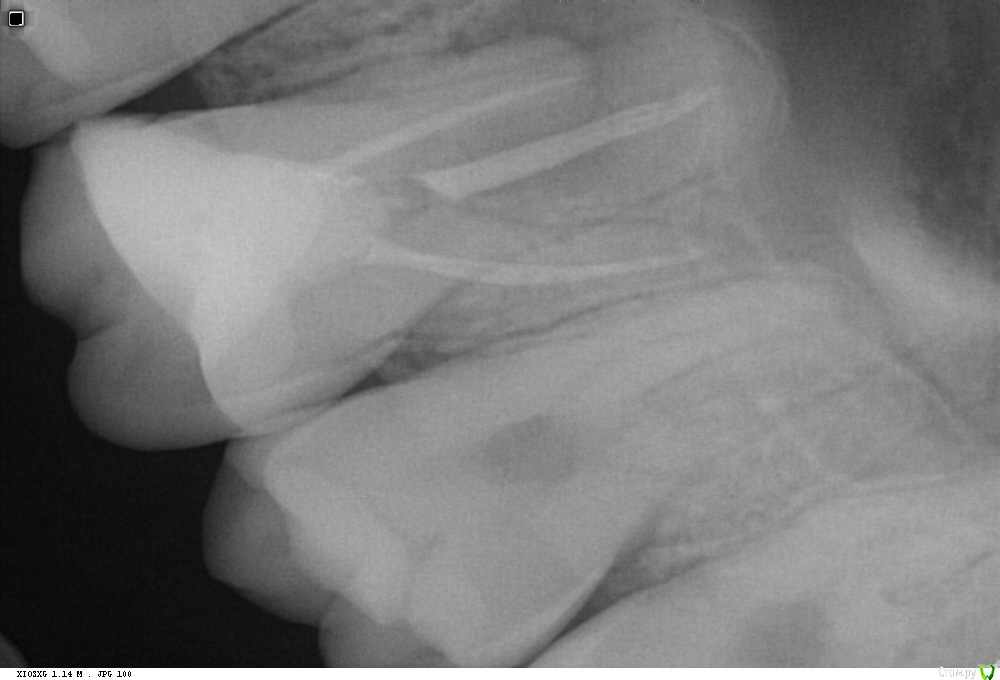

229KAMA Опубликовано 24 октября, 2016 Поделиться Опубликовано 24 октября, 2016 Пришел пац, от ортопеда, пан, или пропал, сломан в канале титановый штифт, что думаете делать?Оптики нет...Обязательно попытайтесь. Даже без увеличения шансов что сможете получить положительный результат очень велики.Вопервых по снимку отломок в ровном канале,в средней трети(даже более коронарнее),сам канал прямой есть возможность для маневра,если не ошибаюсь верхний центральный резец.Сначала пикой алмазной очень акуратно (я это делаю ультрозвуком, иногда наконечником но на малых оборотах) но и на глубину ну скажем так не более чем 0,5 -0,3мм по периметру обломка пройтись. Так чтобы отломок как пенек торчал в просвете канала. Далее эндочаком водите по этой канавке врашаясь вокруг обломка желательно врашения на отвинчивание резьбы.(если есть) если нет резь бы а просто насечки всеравно врашательные движения и иногда прямо по самому обломку секунд 5-6 постукивать. Долго , нудно , не сильно давите , мойте ,(я реже с водой просто долблю) визуальный контроль вашей уз долбежки и предположительно через час или полтора обломок может выпрыгнуть из канала.(может и намного раньше.) Если без воды уз гоняете , незабудте о том что насадка греется и необожгите пациента это так к слову , думаю все итак сами знаете.Обязательно попытайтесь. 1 Ссылка на комментарий